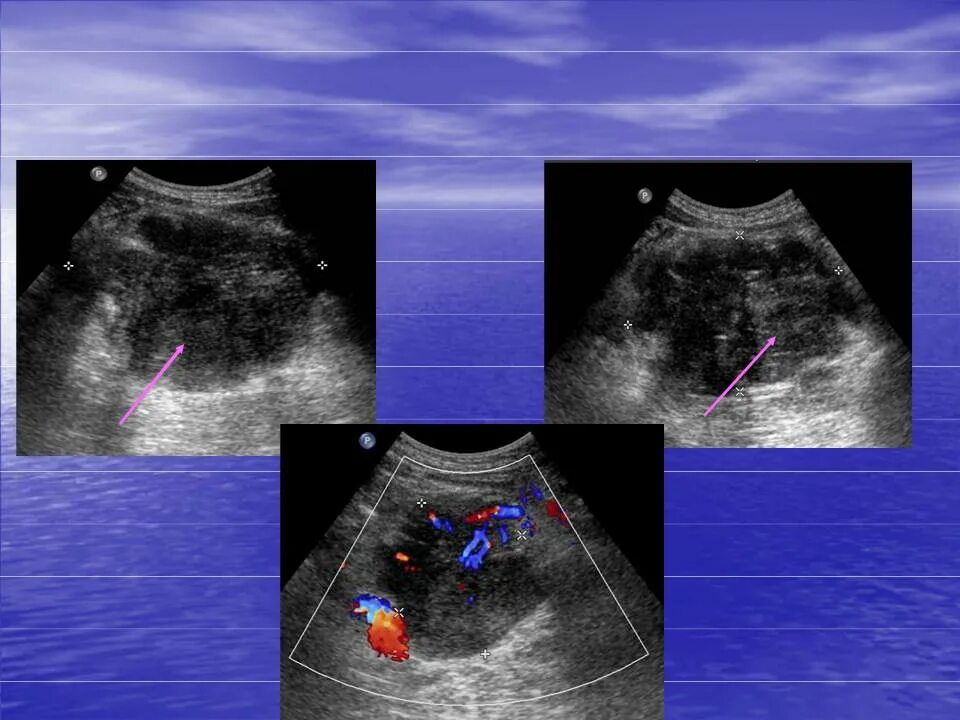

Лучевая терапия метастазов в лимфоузлах